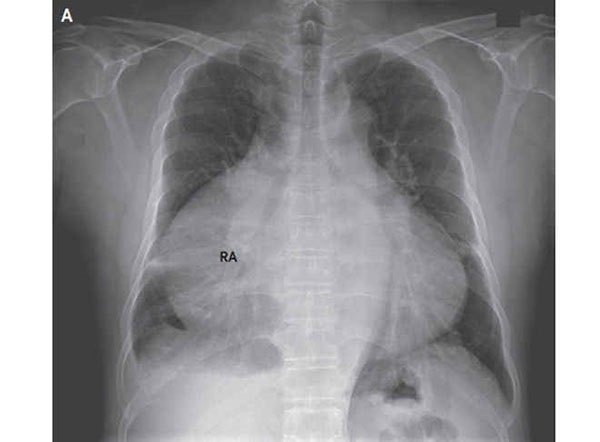

به گزارش همشهری آنلاین و به نقل از لايوساينس، پزشكان با تصويربرداريهاي مكرر از قفسه سينه اين بيمار دريافتند دهليز سمت راست قلب وي، يكي از چهار حفره قلبي، به شدت بزرگ شدهاست.

به دليل بزرگشدن دهليز، نسبت قلبي سينهاي اين مرد به 0.82 رسيدهبود. اين نسبت براساس پهناي قلب در برابر پهناي قفسه سينه به دست ميآيد. به بياني ديگر قلب اين مرد 82 درصد از فضاي عرضي درون قفسه سينه او را اشغال كردهاست. نسبت عادي قلب به قفسه سينه بايد 0.5 باشد، يعني قلب بايد كمتر از 50 درصد از عرض فضاي درون قفسه سينه انسان را اشغال كند.